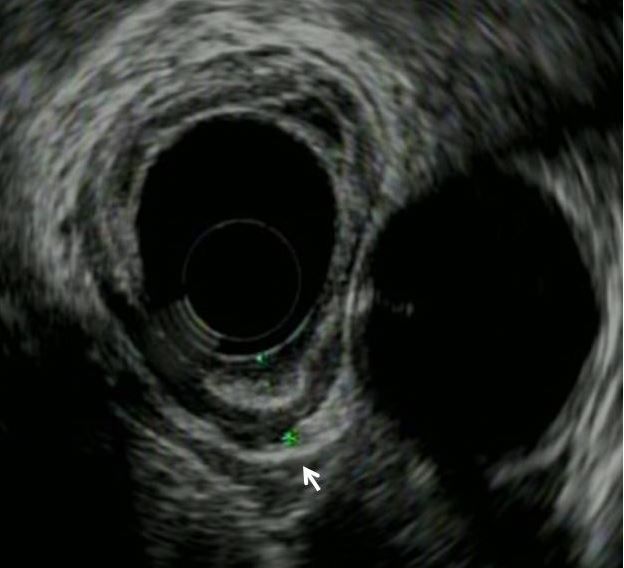

Subsequent endosonographic ultrasonography (EUS) was performed and showed a thickened (7- to 8-mm) gastric wall of the cardia (Figure 3, arrow) with the rest of the stomach showing normal thickness. Endoscopic mucosal resection was performed.